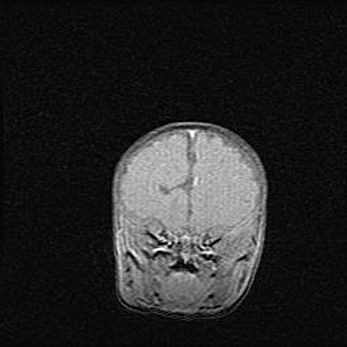

Подострая гематома правой гемисферы мозжечка.

Наружная гидроцефалия.

Возраст: 15 дней

Вес: 3100 г

Пол: женский

Окружность головы: 37 см

Срок гестации: 35-36 недель

При открытой наружной форме гидроцефалии у новорожденных расширяются и переполняются субарахноидные пространства.

Кровоизлияния в мозжечок имеют две клинико-анатомические формы: полушарные гематомы и кровоизлияния в червь.

К появлению этой патологии может привести: повреждения головного мозга, возникающие в результате асфиксии и гипоксии плода при беременности, или травмы во время родов. Редко гематома мозжечка может быть результатом первичной коагулопатии и сосудистой мальформации, диссеминированном внутрисосудистом свертывании, изоиммунной тромбоцитопении.